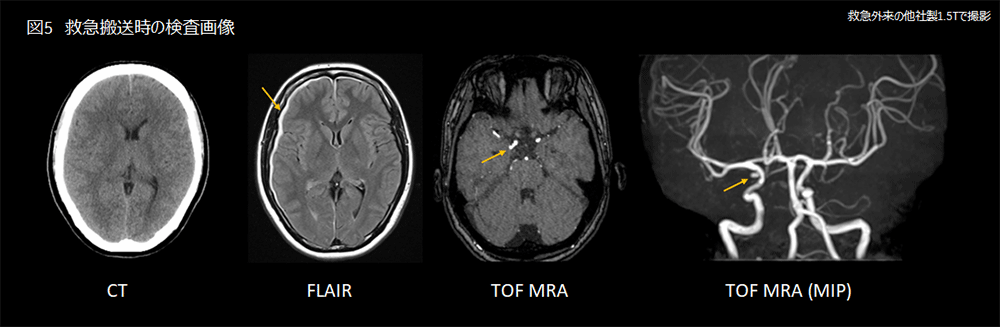

30代女性。突然の激しい頭痛を主訴に救急搬送。頭部CT検査で明らかな出血は認められなかった。頭痛症状が持続しているためMRI検査を施行し、FLAIRにて右硬膜下に薄い血腫を認め、MRAにて右内頸-後交通動脈に動脈瘤を認めた(図5)。その後、3D CTAも施行し同様に右内頸-後交通動脈の先端に歪な形の瘤が認められ、脳表血管には明らかな奇形は認められなかった。

Architect_Okazakishimin_06.png